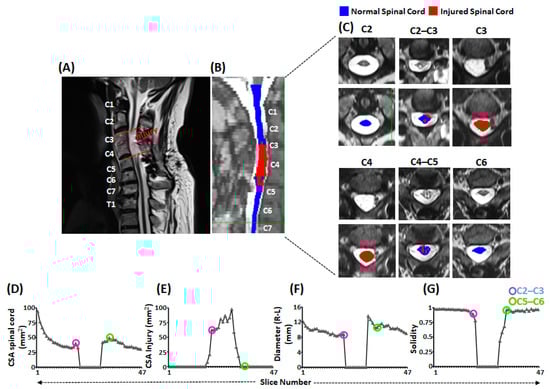

3.1. Severity of Injury

- Rejc, E.; Smith, A.C.; Weber, K.A.I.; Ugiliweneza, B.; Bert, R.J.; Negahdar, M.; Boakye, M.; Harkema, S.J.; Angeli, C.A. Spinal Cord Imaging Markers and Recovery of Volitional Leg Movement With Spinal Cord Epidural Stimulation in Individuals With Clinically Motor Complete Spinal Cord Injury. Front. Syst. Neurosci. 2020, 14, 559313. [Google Scholar] [CrossRef]

- Smith, A.C.; Angeli, C.A.; Ugiliweneza, B.; Weber, K.A.; Bert, R.J.; Negahdar, M.; Mesbah, S.; Boakye, M.; Harkema, S.J.; Rejc, E. Spinal cord imaging markers and recovery of standing with epidural stimulation in individuals with clinically motor complete spinal cord injury. Exp. Brain Res. 2021, 240, 279–288. [Google Scholar] [CrossRef]

- Sharma, P.; Naglah, A.; Aslan, S.; Khalifa, F.; El-Baz, A.; Harkema, S.; D’Amico, J. Preservation of functional descending input to paralyzed upper extremity muscles in motor complete cervical spinal cord injury. Clin. Neurophysiol. 2023, 150, 56–68. [Google Scholar] [CrossRef]